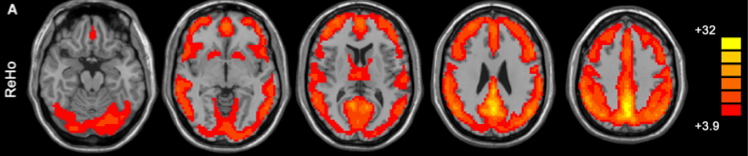

The figure above (taken from Yan and Zang, 2010) shows the default mode network as detected by ReHo analysis (colors indicate t values).